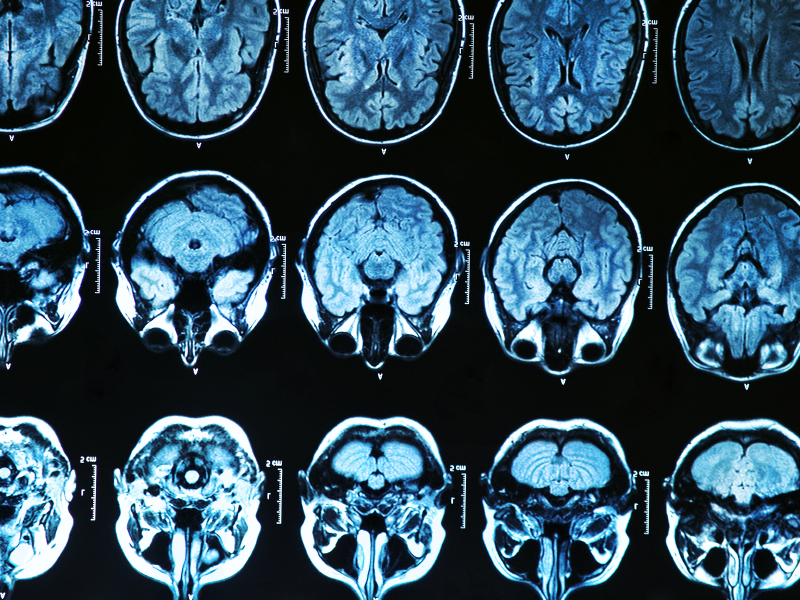

3) Correlatos neurais de pistas sexuais reativas em indivíduos com e sem comportamentos sexuais compulsivos (2014)

Link para o artigo: http://journals.plos.org/plosone/article?id=10.1371/journal.pone.0102419

7) Apetite alterado por condicionamento e conectividade neural em indivíduos com comportamento sexual compulsivo (2016)

Link para o artigo: http://www.jsm.jsexmed.org/article/S1743-6095%2816%2900111-9/fulltext

8) A estrutura cerebral e conectividade funcional associada ao consumo Pornografia: O cérebro e a pornografia (2014)

Link para o artigo: http://archpsyc.jamanetwork.com/article.aspx?articleid=1874574